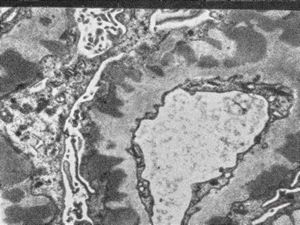

M,29y. | type II membranoproliferative glomerulonephritis (dense deposit disease)